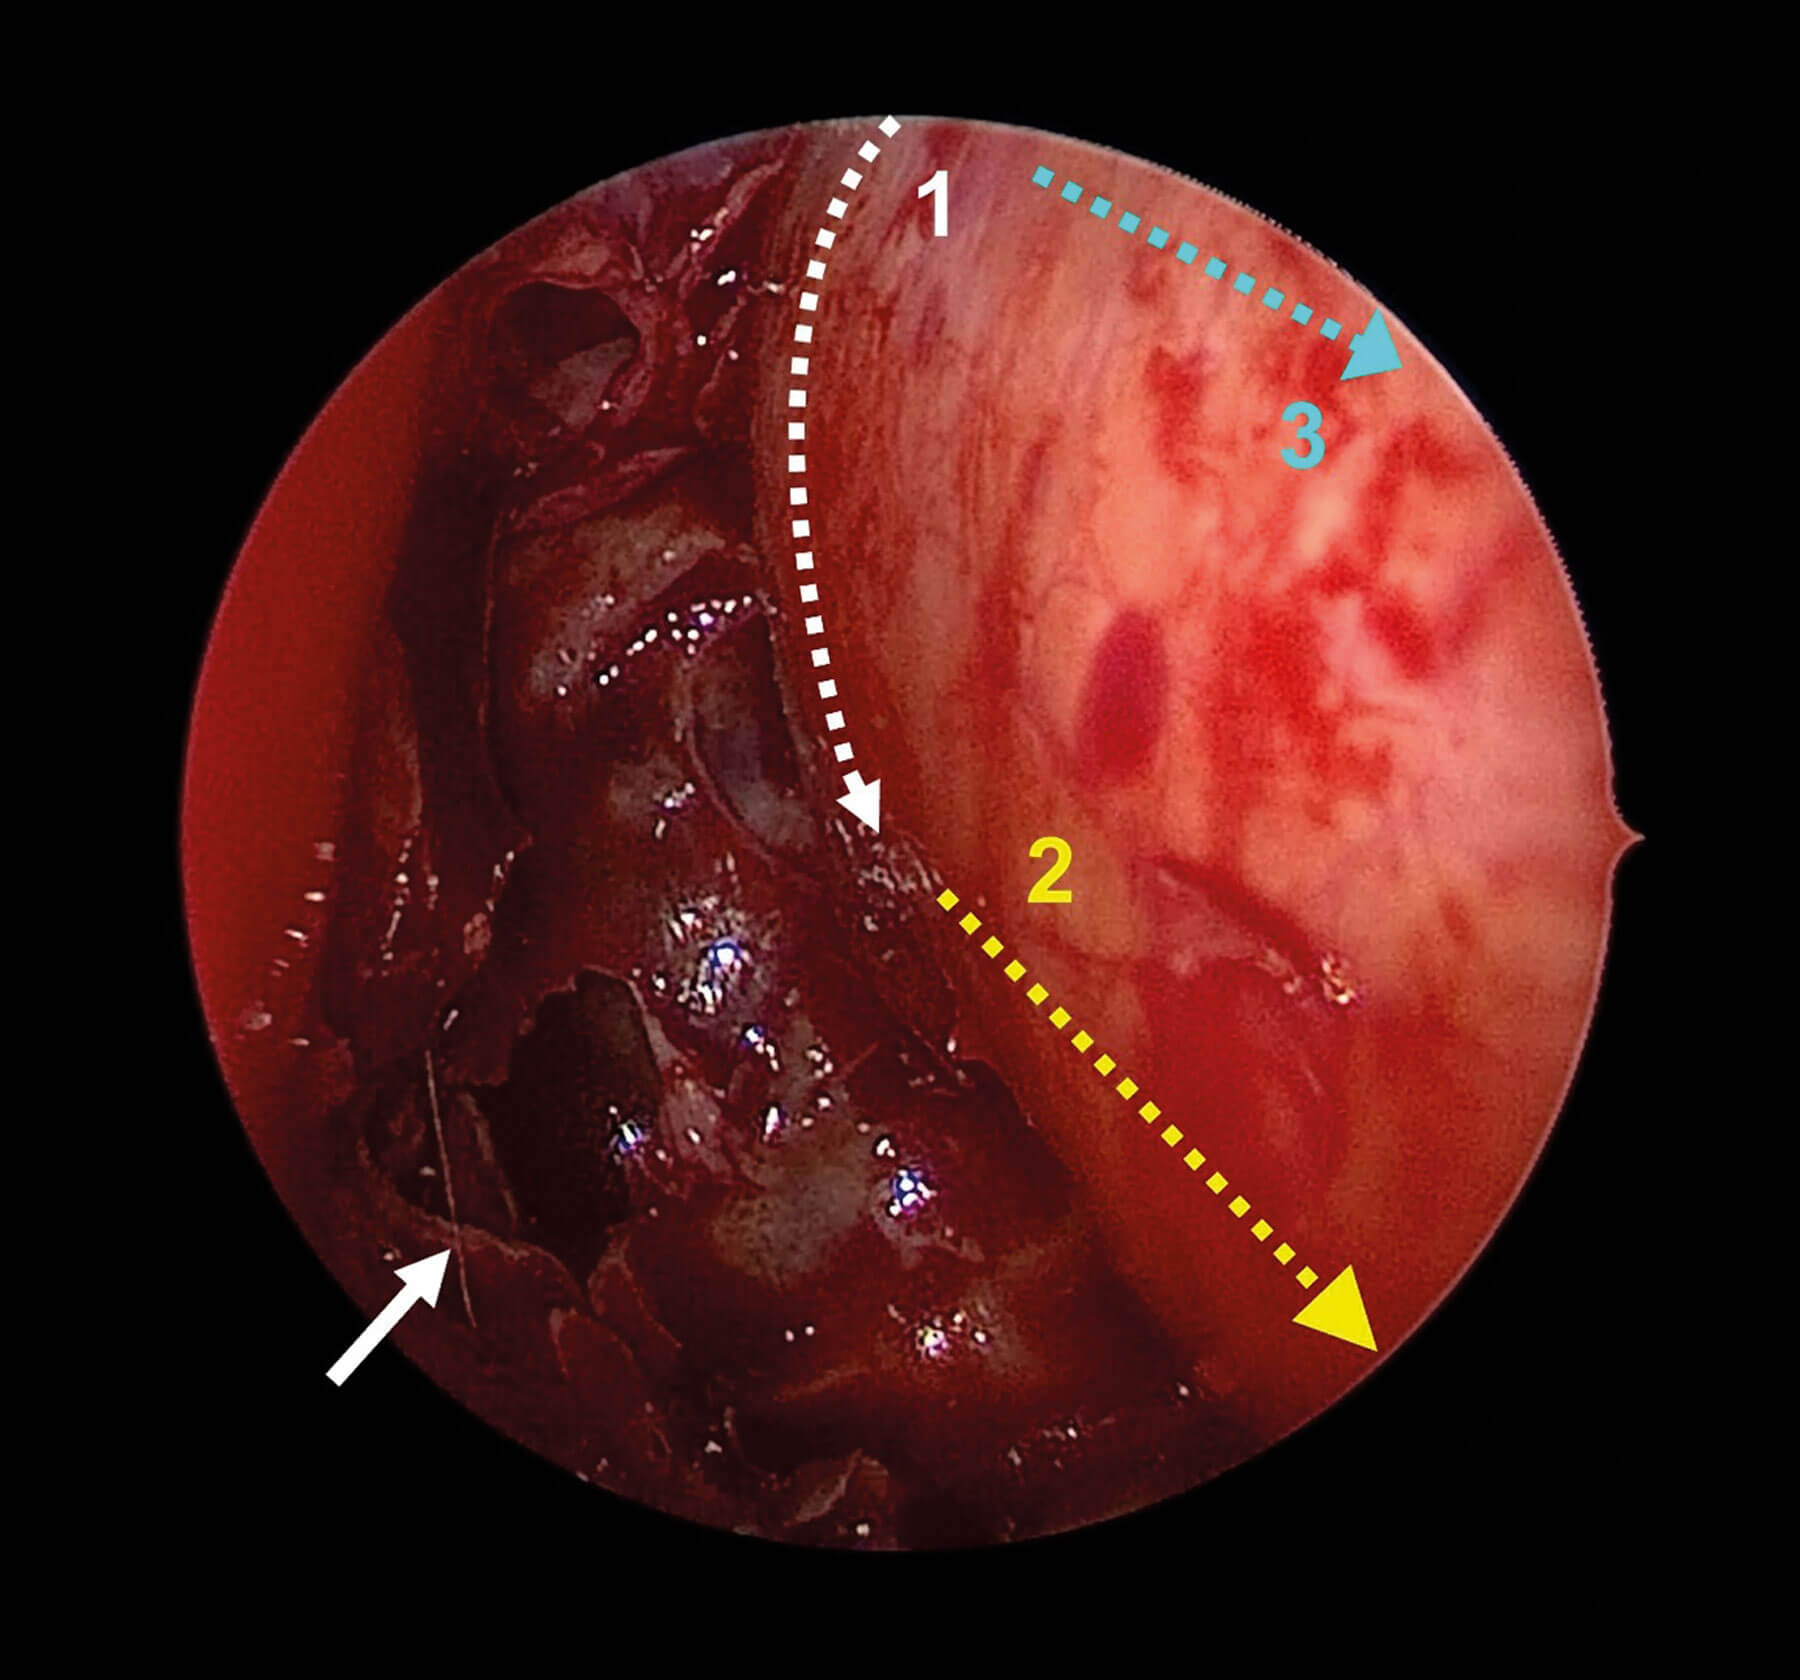

Figure 1. Endoscopic view of the left nasal cavity following anterior and posterior ethmoidectomy.

The lamina papyracea has been removed, revealing the bulging periorbita. Asterisk = face of sphenoid.

White arrow = frontal recess. Yellow arrow = maxillary sinus with excised orbital floor superiorly.

Figure 2. Demonstration of periorbita incisions. 1 = vertical incision using phaco knife.

2 = inferior incision using sickle knife. 3 = superior incision using sickle knife. White arrow = sphenoid ostium.

Step 5 - incision of periorbita

A phaco slit knife is used to make a vertical cut at the posterior limit of the periorbita. The orbital apex is just lateral at this point, so great care must be taken to avoid damaging the medial rectus muscle and optic nerve through an overly deep incision. Once the tip of the blade is through the periorbita, the cut is performed from lateral to medial to reduce the risk of injury to these structures. A sickle knife is then used to make posterior-to-anterior cuts inferiorly and then superiorly, at which point the orbital fat will begin to prolapse into the nasal cavity. This sequence prevents prolapsing fat from obscuring the surgeon’s view. A ball-point probe is used to release any remaining bands of fibrous tissue anchoring the periorbita to the orbital fat. The periorbita is removed as infero-laterally as possible to ensure a full release through the orbital floor into the maxillary sinus.